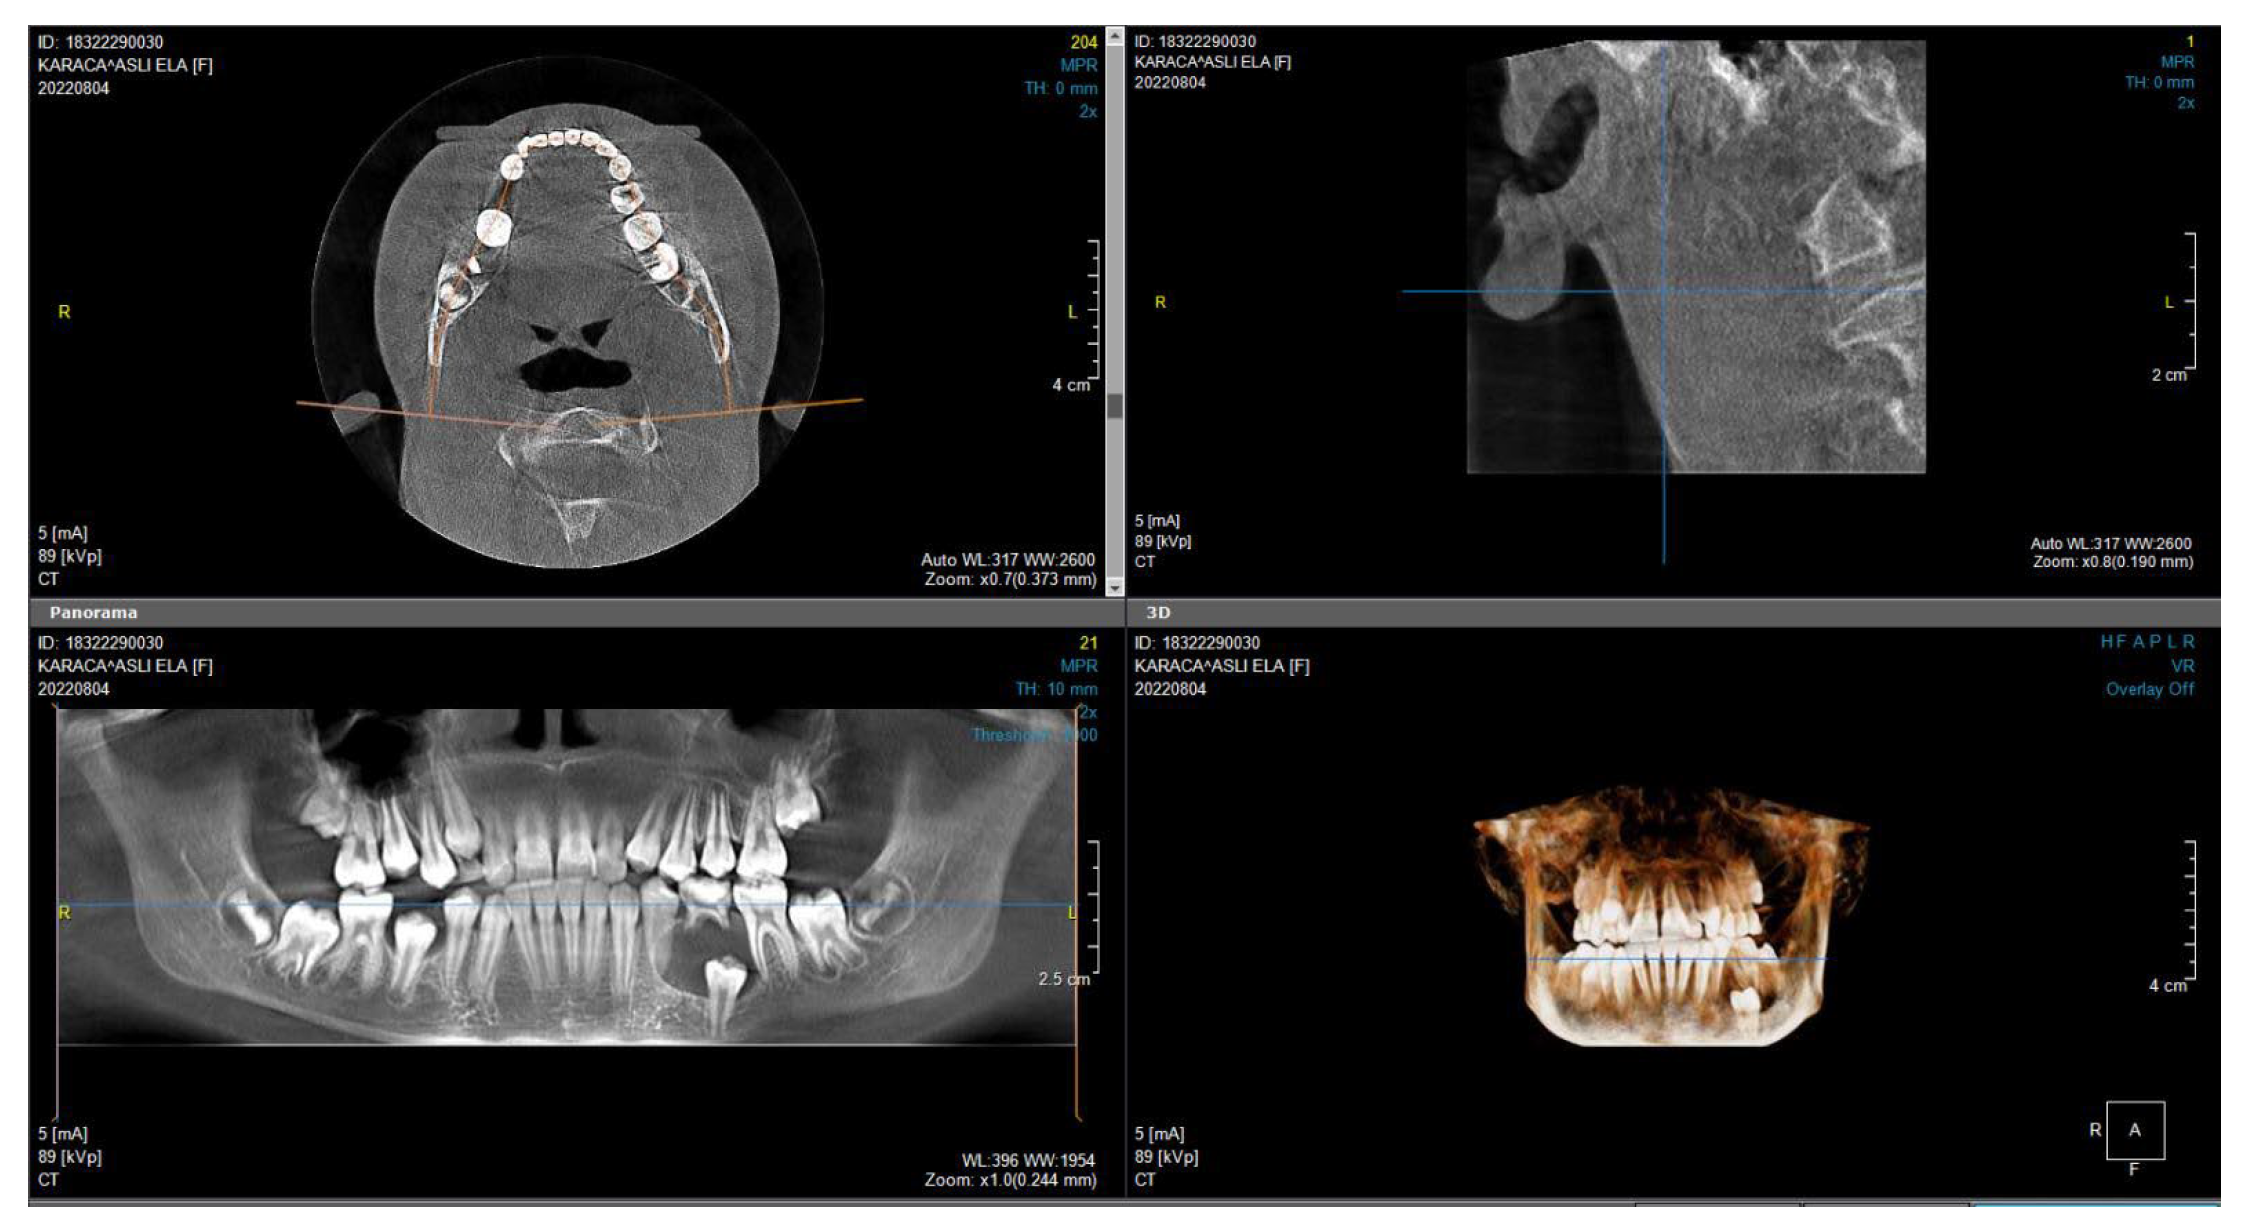

2. Materials and Methods